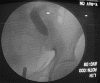

Genitourinary tract arteriovenous malformations are extremely rare. Most of the lesions are found either in the kidney or urinary bladder. So far, to the best of our knowledge, only five cases of arteriovenous malformation of the ureter have been reported in the literature. Here, we present, a young male, clinically presented with pain in the left flank with no other significant history. On radiological evaluation found to have left hydroureteronephrosis with stricture of the left distal ureter at the level of iliac vessel crossing. Urine routine, cytology, and cystoscopy were unremarkable. Left retrograde pyelogram showed distal ureteric stricture. Patient underwent excision of left distal ureteric stricture segment and ureteric reimplantation with psoas hitch. Histopathological examination revealed the features of arteriovenous malformation of the left ureter. The patient is asymptomatic and has no recurrence on follow-up until 12 weeks after surgery.